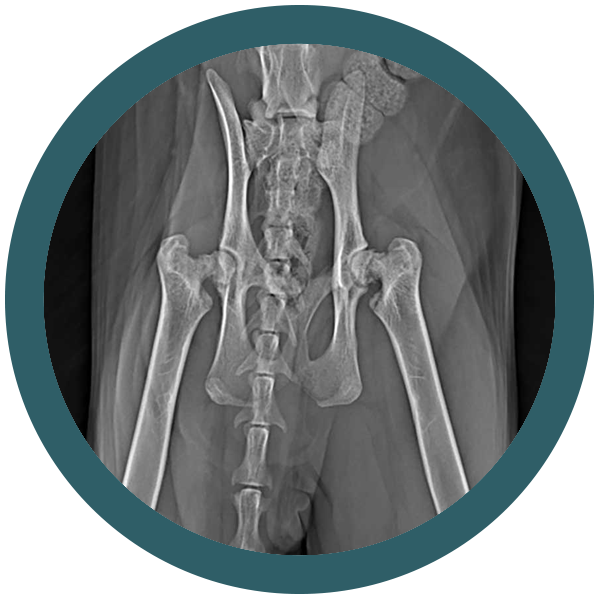

Il tuo gatto è un compagno fedele e amorevole che ti dà gioia ogni giorno. Ma anche i gatti possono soffrire di problemi ortopedici.

La buona notizia è che ci sono molti modi per prevenire i problemi ortopedici nei gatti. Una dieta sana e nutriente, esercizio fisico quotidiano e controlli regolari dal veterinario possono aiutare a mantenere il tuo gatto in forma e sano. Ma cosa succede se il tuo gatto ha un problema ortopedico? In questo caso interveniamo noi di Ortovet.

Siamo una rete di specialisti ortopedici veterinari e offriamo un servizio di elevata qualità, con l’utilizzo delle tecniche chirurgiche più avanzate. I nostri medici veterinari sono esperti nel trattamento di una vasta gamma di problemi ortopedici nei gatti

Come riconoscere una displasia dell’anca nel gatto